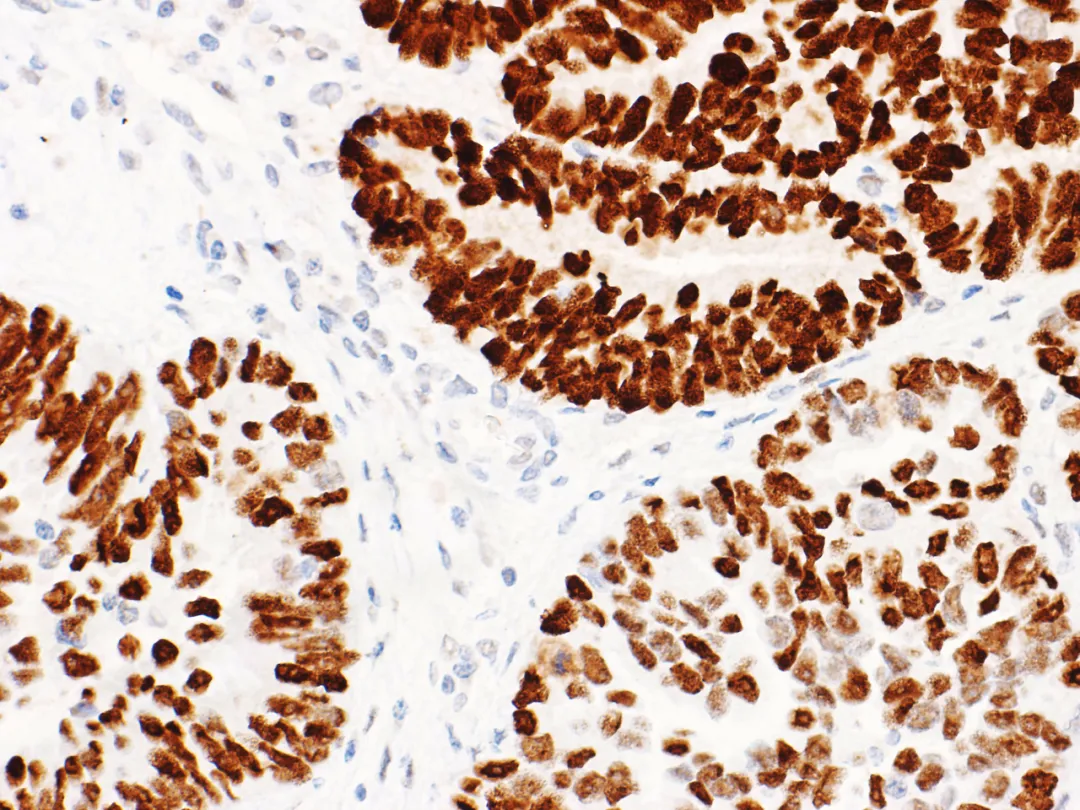

p53 immunohistochemistry can predictTp53gene mutation in endometrial cancer (as shown in Figures 4 and 5).The heterogeneity of endometrial cancer makes interpretation difficult in approximately 5% of cases, and most of these cases are associated with POLE mutation or MMR deficiency.

Figure 5. Endometrial cancer – Mutant p53 nuclear overexpression